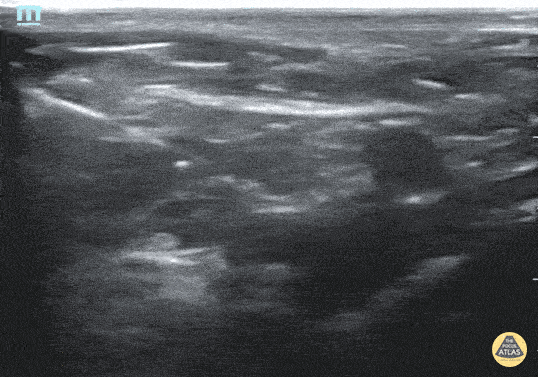

Fascia iliaca nerve block for 3 yo M with left femur fracture. Contributor: Julia Brant, MD, Children's Hospital Colorado, @pedipocus